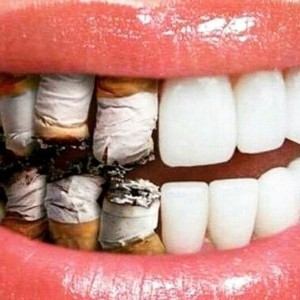

עשן הסיגריה מכיל כששת אלפי כימיקלים שונים , כ70 מהחומרים ידועים כחומרים קרציוגינים (מסרטנים) ושניים מהם הבנזופ�...